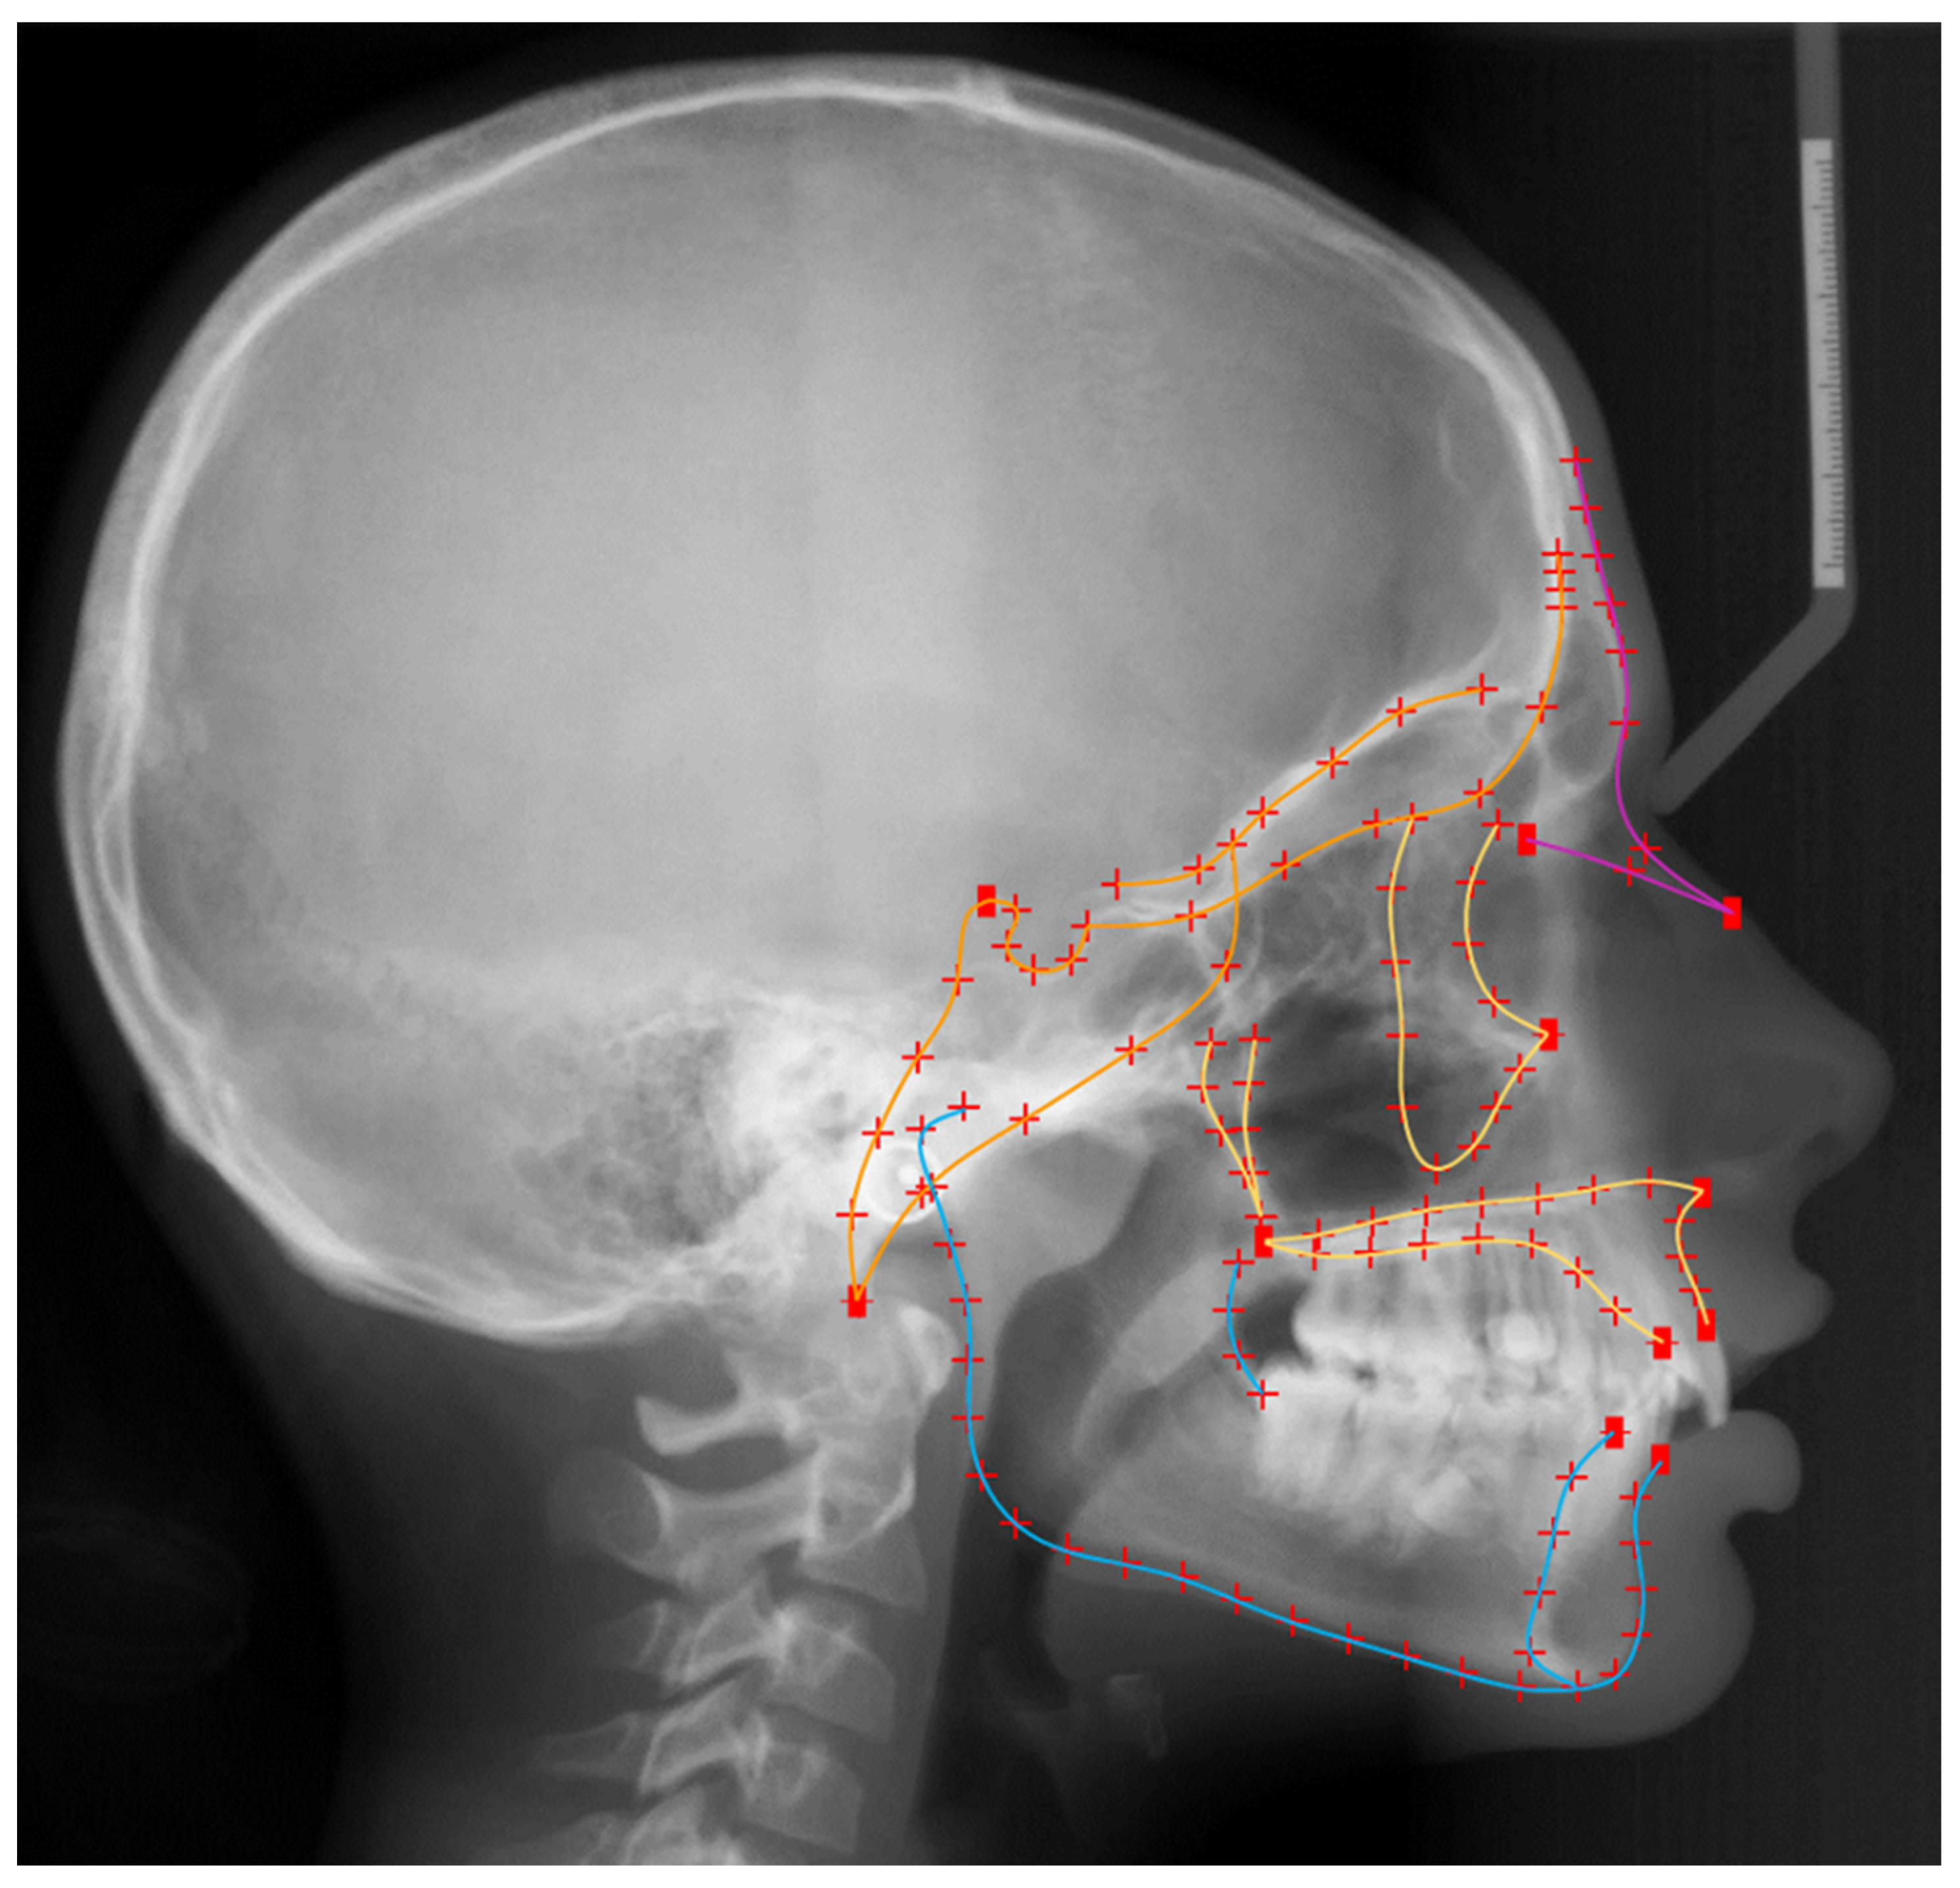

- Lateral cephalometric radiographs in maximal intercuspation, of diagnostic quality, with a reference ruler at the mid-sagittal plane for magnification adjustment

2.4. Size Assessment